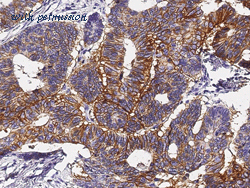

gene information - human A33

- A33 antibody